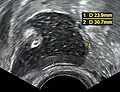

A complex cyst due to a dermoid as seen on ultrasound